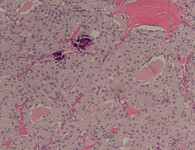

Histopathology of papillary carcinoma, thyroid: a psammoma body is visible (arrow)

CDC Image Library/Dr Edwin P. Ewing, Jr